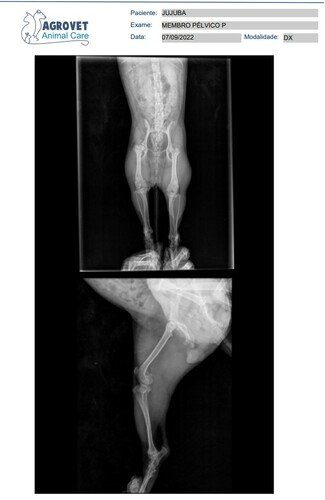

Infelizmente fui diagnosticada e sofro de uma doença chamada “ Necrose asséptica da cabeça femoral direita ” , isso faz com que eu sinta muita dor e faz com que eu ande mancando o tempo todo, não consigo brincar e nem pular direito, não consigo ficar em pé, pois dói bastante. Infelizmente minha mamãe e meu papai no momento não tem condições para arcar com todo o valor da cirurgia, pois tem a cirurgia e também os gastos com a pós cirurgias, fisioterapia e tudo mais … E conforme o tempo passa, esse problema vai afetando ainda mais outras partes do meu corpinho…